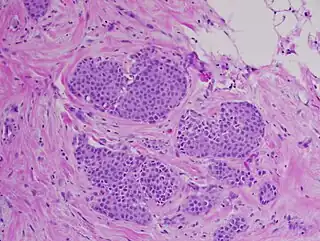

![]() Carcinoma lobulillar 'in situ', tinción hematoxilina-eosina, 20x | ||

El CLIS es una proliferación sólida y oclusiva de los lobulillos y otros conductos perilobulillares. Los acinos de las glándulas se ven dilatados y ocupados por células pequeñas y por lo general uniformes, siendo pleomórficas solo en la afectación ductal del carcinoma, es decir, cuando aparece en los conductos mamarios. Estas células no han invadido los tejidos más profundos del seno, ni se han propagado a otros órganos del cuerpo.[2] Rara vez se ve necrosis o calcificación y de aparecer ocurre en las etapas más avanzadas de la enfermedad.[4]